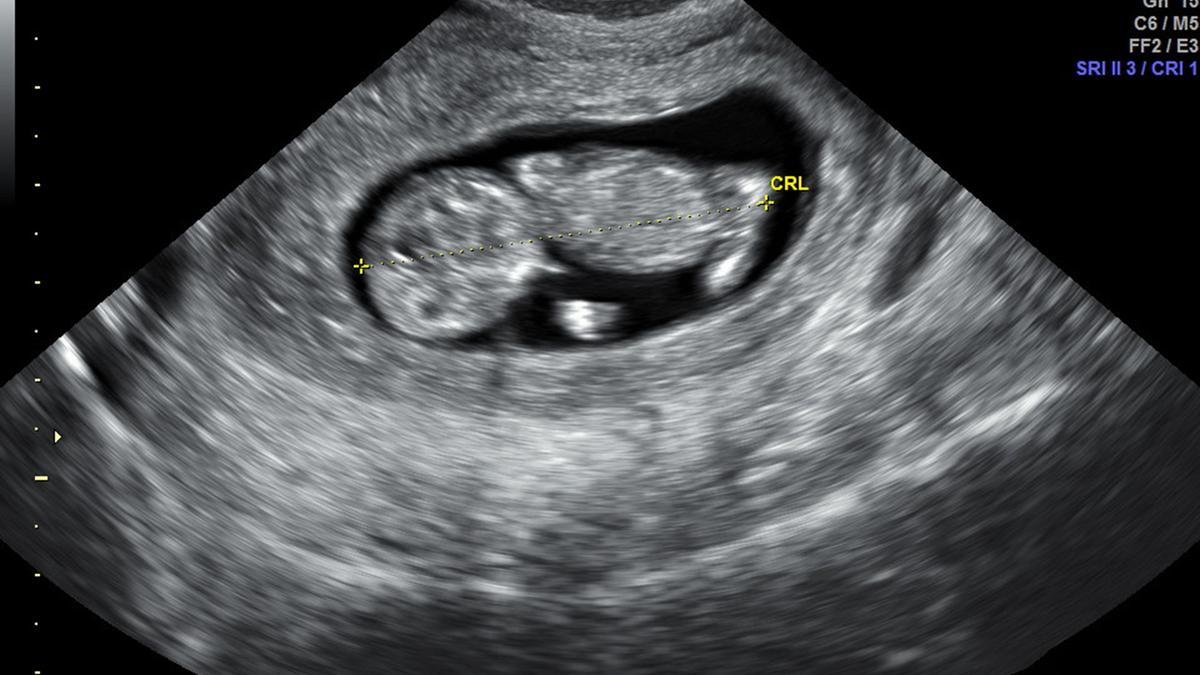

Ecografía de las 12 semanas del bebé que no pudo tener la vecina de Plasencia. / EL PERIÓDICO

Querían tener un bebé. Iban a tener una niña, pero todo se torció con la ecografía de las 20 semanas y el calvario que esta vecina de Plasencia vivió desde entonces la ha «destrozado». Más de ocho meses después de un aborto que no querían, pero al que las circunstancias les obligaron, ella tiene fuerzas para contarlo y para denunciar el «desamparo, abandono, humillación y deshumanización» que ha vivido por parte del sistema sanitario público extremeño, una forma de violencia obstétrica que quiere dar a conocer «para ayudar a otras mujeres en mi situación y que nadie más tenga que pasar por lo que yo he pasado. Lo hago por el legado de mi hija».